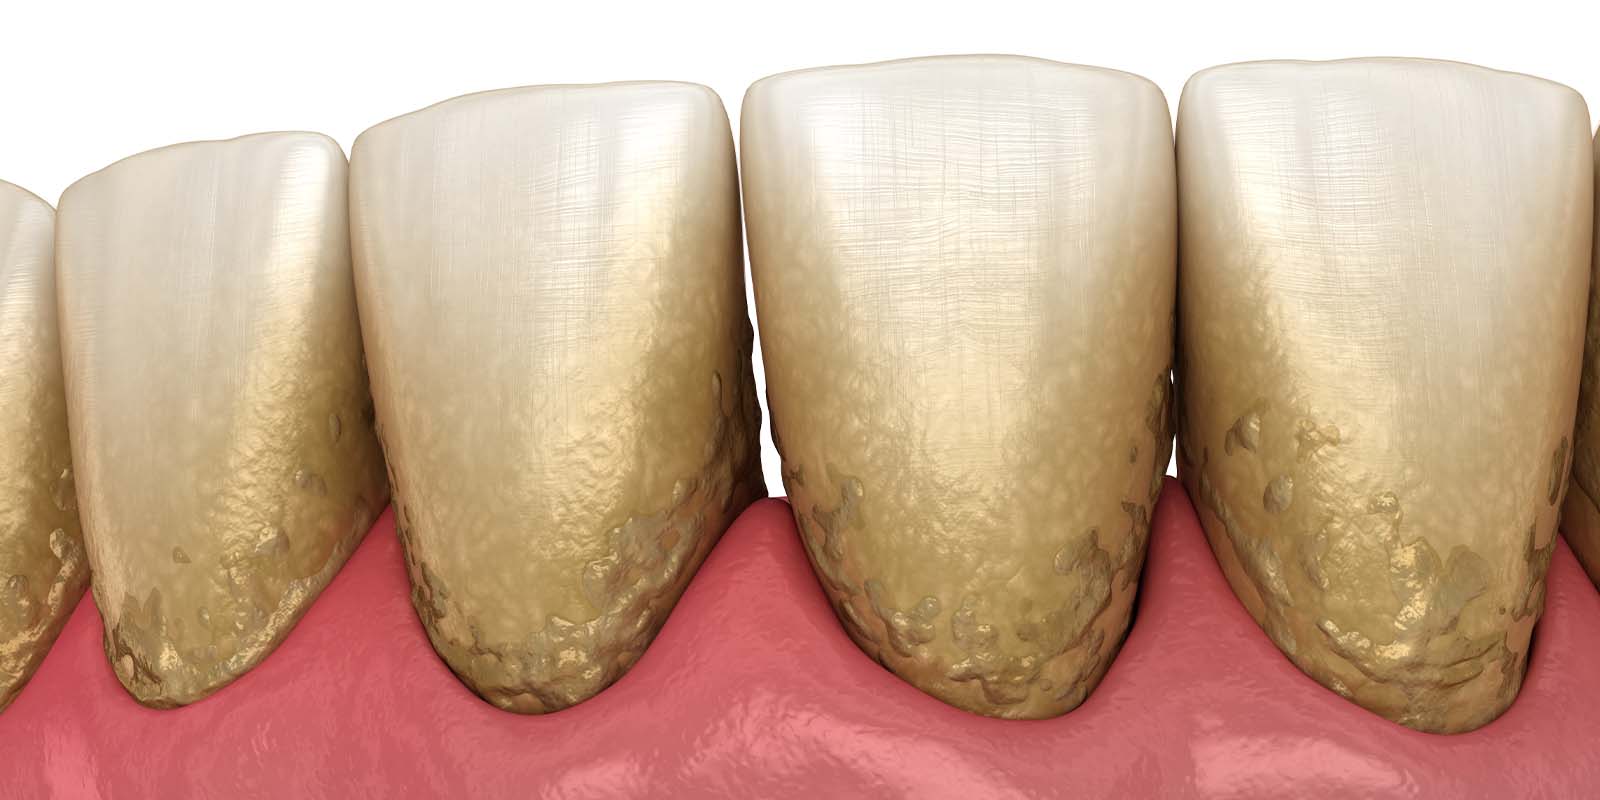

歯周病になる原因

歯周病になる1番の原因は「磨き残し」です。

磨き残しのことを歯科用語では、歯垢(しこう)またはプラークといいます。

プラーク1mgのなかには、およそ300種類1億個の細菌が存在しており、歯ぐきに付着することで炎症を引き起こします。これが歯肉炎の始まりです。

つまり、お口の中に細菌が多い状態が続くと歯肉炎、歯周病の原因になります。

2. スケーリング(歯石除去)

歯科医院で行うクリーニングの中に含まれるもので、専用の機械や器具を使用して歯石を取り除きます。

歯石の表面にはざらつきがあり、プラークが溜まりやすくなるため定期的に除去しましょう。

スケーリングで歯石を除去する重要性

歯石は歯垢(プラーク)が石灰化したものです。

大量の細菌が含まれていますが、歯ブラシの力では除去することができません。

特に歯周病の場合は、歯ぐきの中に歯石が入り込むため、気づかずに放置してしまう方も少なくないのです。

歯周病を悪化させないためにも、定期的なクリーニングで歯石の除去をおすすめします。